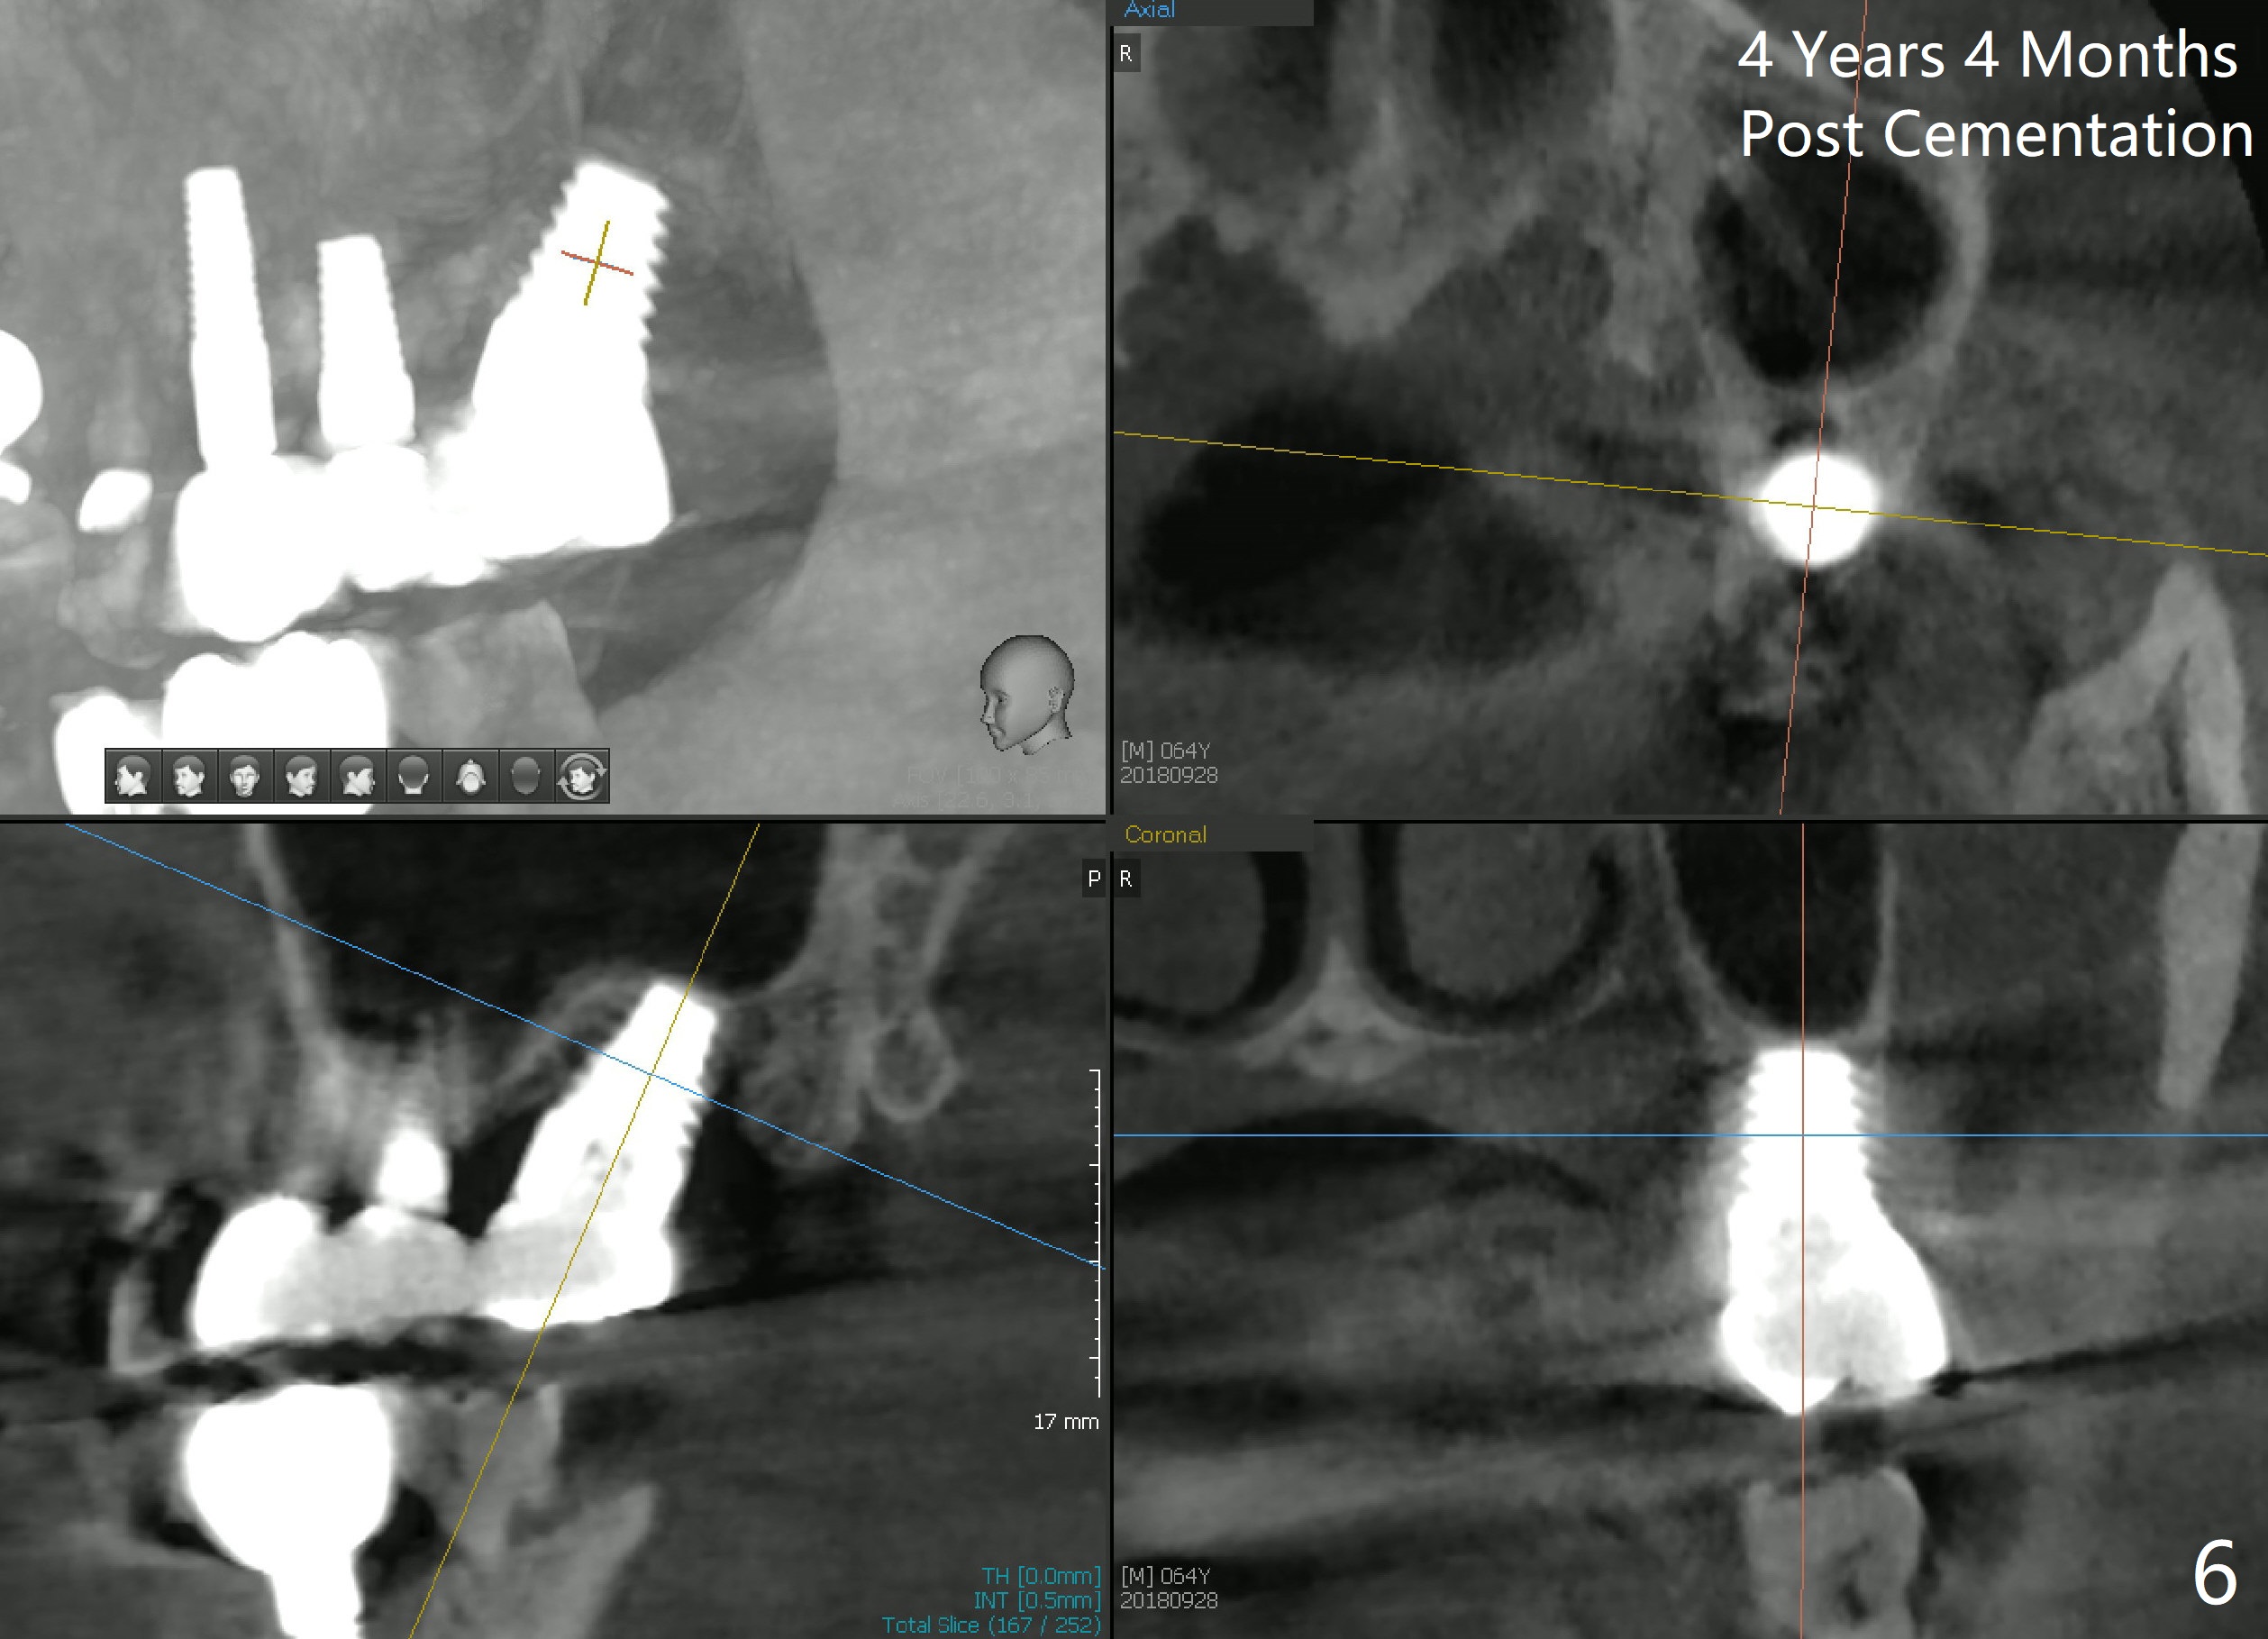

In fact, a tapered tap of 8x14 mm was used (Fig.4 T) before the implant of equivalent size was placed (Fig.5: I). The patient and the implant are doing fine after surgery. No bone loss is noted 4 years 4 months post cementation (Fig.6).